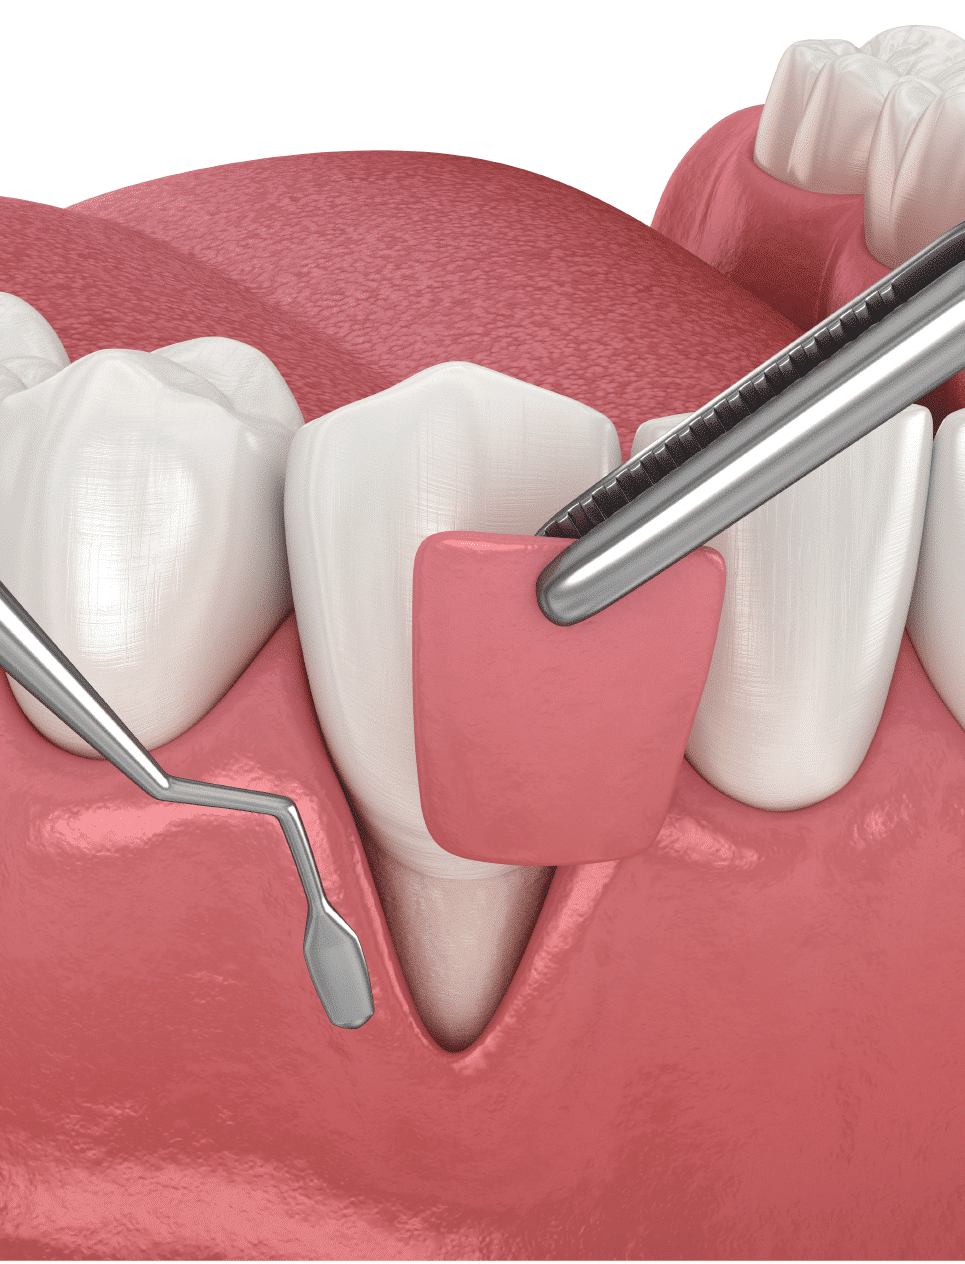

What Are Soft Tissue Grafting Procedures Like?

Gum tissue is borrowed from four different sources. One, a thin piece of tissue is taken from the roof of the mouth. Two, if there is extra tissue around the upper wisdom tooth area, sometimes this can be used for the graft. This extra tissue can create a pseudopocket around the tooth in front of the wisdom tooth which can lead to periodontal disease. Commonly removing this tissue solves two problems – the need for a graft and the need to prevent future periodontal disease on an upper back tooth. Three, Gum tissue can also be gently moved over from adjacent areas to provide a stable band of attached gingiva around the tooth.